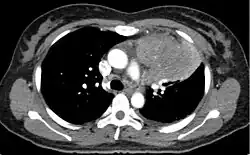

Hinweise auf ein Thymom ergeben sich schon im Röntgenbild des Brustkorbes bei Vorliegen einer unklaren vorderen mediastinalen Raumforderung. Es zählt zu den mnemotechnisch oft zitierten vier T’s in der Differentialdiagnostik der vorderen mediastinalen Raumforderungen (Teratom, Thymom, Glandula thyroidea und „terrible lymphoma“). Zur Standarddiagnostik gehört die Computertomographie (CT). Zur Unterscheidung von gutartigen und bösartigen Tumoren ist stets die Entnahme einer Gewebeprobe (Biopsie) und deren feingewebliche Untersuchung nötig.